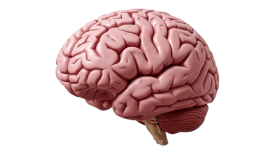

Detailed 3d rendering of the human brain with cerebellum and brainstem

human brain anatomy cerebrum cerebellum brainstem neurology medical illustration science biology organ central nervous system lobes gyri sulci model 3d rendering realistic health cognition mind thinking learning memory function neuroscienceSimilar Photos

- Photo type PNG

- Resolution 2668x1454

- Category Health / Medical

- File size 278.7kB